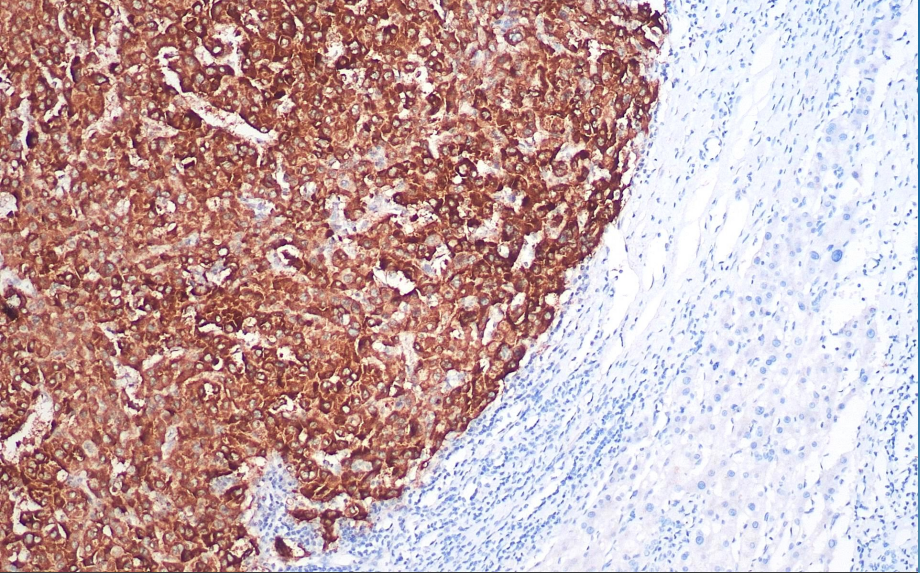

Positive control: Liver cancer

Glypican-3 is a heparan sulfate glycoprotein and a cancer embryonic antigen. The gene encoding this protein is located on Xq26. Overgrowth syndrome (Simpson-Golabi-Behmel syndrome) is associated with a deletion of this gene. Glypican-3 is expressed in embryonic liver, kidney, and lung tissues, as well as in the trophoblast layer of placental tissue. In tumor tissues, Glypican-3 expression is observed in hepatocellular carcinoma, yolk sac tumors, choriocarcinoma, and melanoma, but not in other tissues. Current literature recommends its use in combination with CD34 for research on benign and malignant hepatocellular tumors.

Glypican-3 antibody reagents can specifically bind to Glypican-3 molecular antigens. Immunohistochemistry kits containing Glypican-3 antibody reagents are suitable for the precise diagnosis of liver cancer, yolk sac tumors, choriocarcinoma, and melanoma.